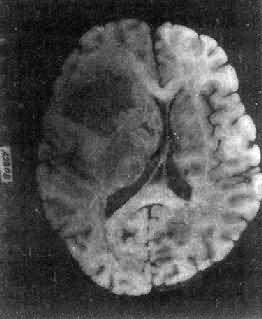

高度恶性的星形胶质细胞称为多形性胶质母细胞(glioblastoma multiforme),多见于成人。肿好发于额叶、颞叶白质,浸润范围广,常可穿过胼胝体到对侧,呈蝴蝶状生长(图16-24)。体因常有出血坏死而呈红褐色。镜下,细胞密集,异型性明显,可见怪异的单核或多核巨细胞。出血坏死明显,是其区别于间变性星形胶质细胞的特征。毛细血管明显增生,内皮细胞增生、肿大,可导致管腔闭塞和血栓形成。肿发展迅速,预后极差,患者多在2年内死亡。

图16-24 多形性胶质母细胞

在两半球内肿呈蝴蝶状,边界不清,切面见有出血、坏死及液化